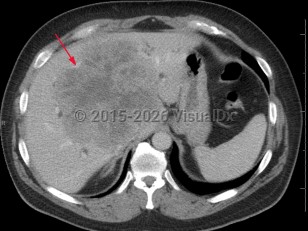

Acinar cell carcinoma is a rare malignant exocrine tumor of the pancreas resembling cells of the pancreatic acini. It comprises less than 1% of all pancreatic neoplasms and is usually a solid tumor. Its gross appearance is a pink to tan homogeneous growth. Tumors may grow to over 10 cm in diameter. Although seen most frequently in males of Northern European ancestry who are middle-aged or older, acinar cell carcinoma can occur at any age.

Findings include abdominal pain, a pancreatic mass, nausea, fatigue, weakness, elevated lipase, and weight loss. Some patients present with Schmid's triad (subcutaneous fat necrosis, polyarthritis, and eosinophilia) caused by elevated lipase secreted by the tumor.

Acinar cell carcinomas can easily be differentiated from adenocarcinoma and pancreatic neuroendocrine tumors based on immunohistochemical stains. Overall prognosis depends on tumor size, lymph node involvement, and presence of metastasis at diagnosis.